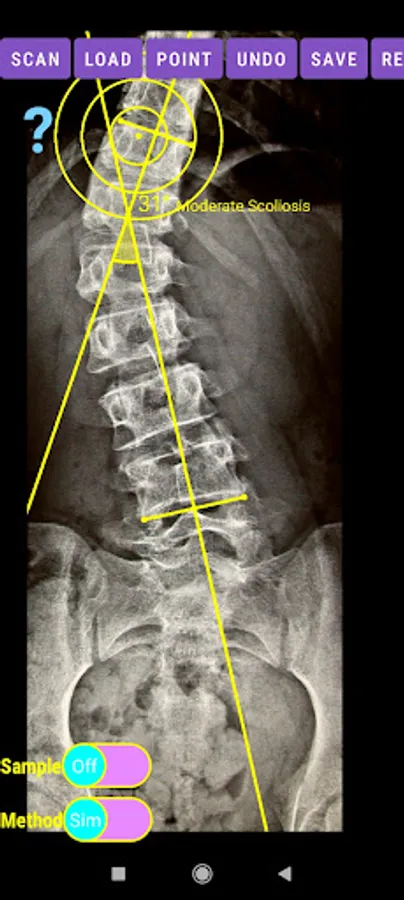

The app offers a very convenient way to asses spinal deformity by measuring the Cobb angle. The first thing is to load one image from your photo library or capture a photo from x-rays photos of a patient. The app offers two measuring methods, the simple (Sim.) and the extended (Ext.). By clicking the relevant option, the option is highlighted and the respective method is activated.

-Offers a very convenient way to determine the most accurate possibly way at once. By marking four points at the same X-ray, at each spine the App calculates the Cobb angle. In cases where values are out of normal ranges, the scoliosis is categorized according to measured angle as mild, moderate, severe. To simplify the process and to minimize inter-observer errors usually by not selecting the actual end vertebra, the app offers also in ext mode the ability to draw the vertical reference line through the patient’s sacrum and to identify more easily the end vertebrae (ext method).